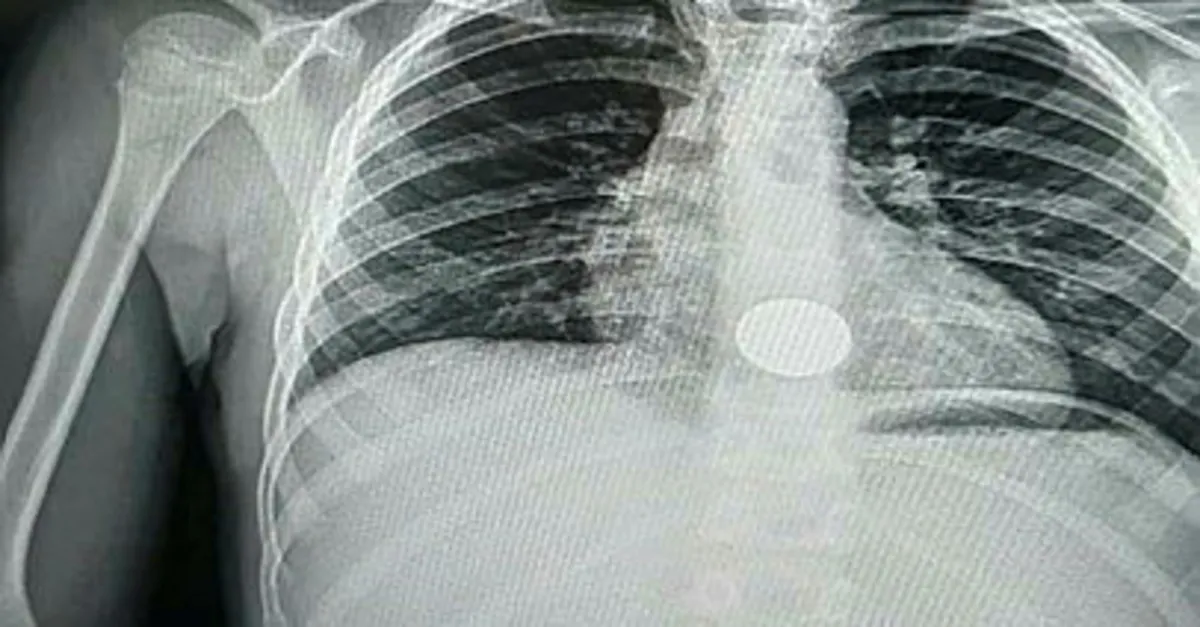

Tire'de oturan Serap ve Hüseyin Kırlı çiftinin oğulları, dün akşam iddiaya göre oyun oynadığı sırada elindeki demir parayı yanlışlıkla yuttu. Durumu fark eden aile, parayı çıkarmaya çalıştı ancak başarılı olamayınca Ali'yi Tire Devlet Hastanesi'ne götürdü. Burada yapılan kontrollerde demir paranın Ali'nin yemek borusunda olduğu tespit edildi. Ege Üniversitesi Tıp Fakültesi Hastanesi'ne sevk edilen Ali Kırlı, ameliyata alındı. Ali'nin yemek borusuna takılan demir para çıkarıldı.

Konuyla ilgili konuşan baba Hüseyin Kırlı, "Oğlum akşam evde oynarken para yuttuğunu söyledi. Hemen hastaneye götürdük. Tire'de ilk müdahale yapıldı, röntgen çekildi fakat operasyon yapılamayacağı söylendi. Ege Üniversitesi Tıp Fakültesi Hastanesi'ne sevk edildik. Orada yapılan operasyonla metal para yemek borusundan çıkarıldı. Şu an eve döndük ve çok şükür sağlık durumu iyi" dedi.